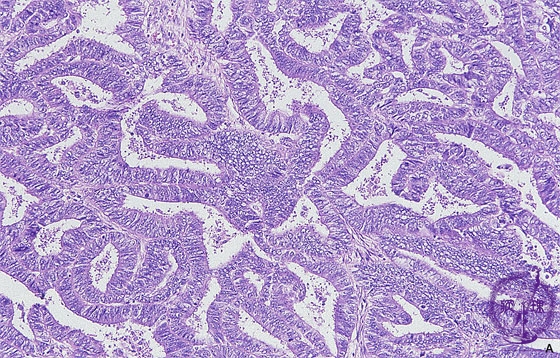

Histology (HE stain, intermediate power): Endometrioid adenocarcinoma of uterine corpus. The most common tissue type. Carcinoma cells mimick the proliferative endometrium.